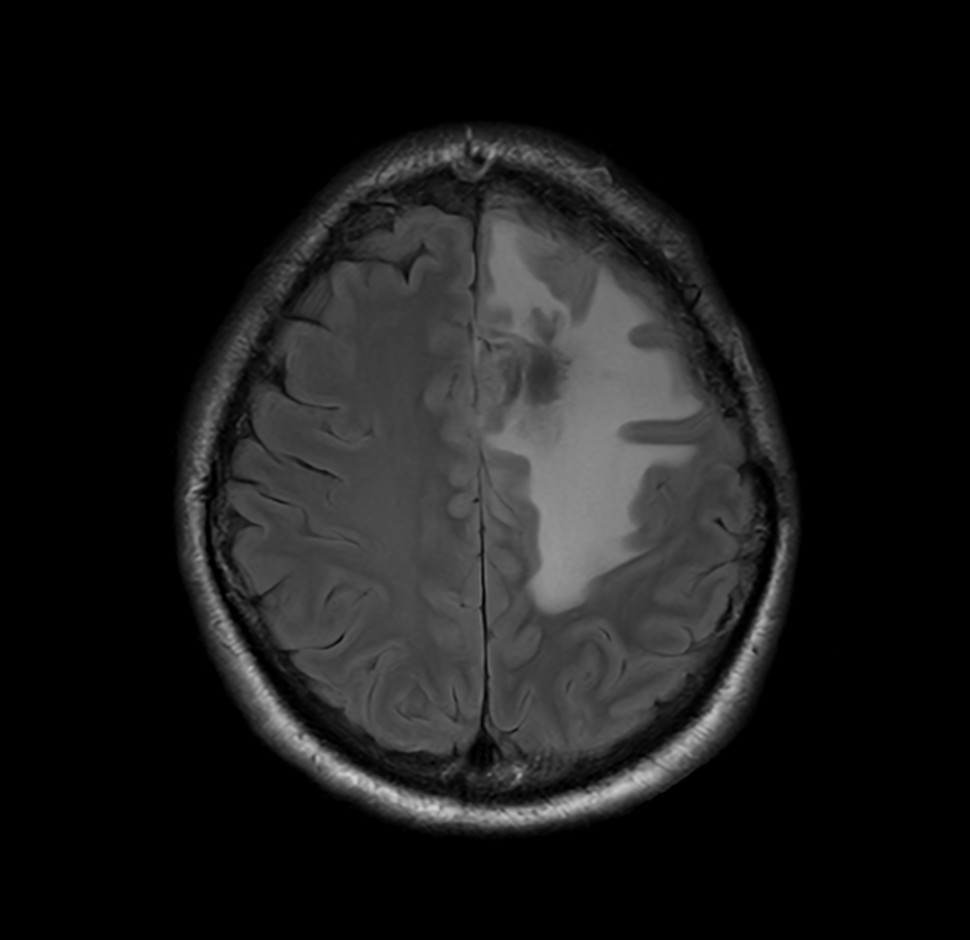

SmartSpeed Precise imaging for brain with glioblastoma

Kyushu University Hospital Japan